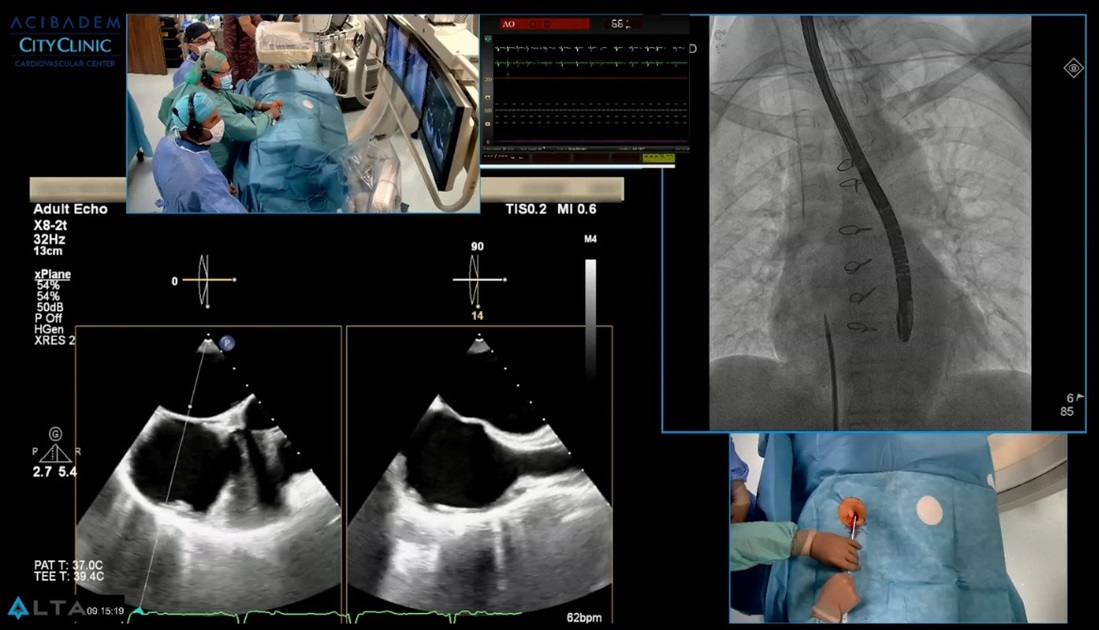

LIVE Case: Имплантация на MitraClip при пациентка с вторична високостепенна митрална инсуфициенция

Пациентката беше финално обсъдена за имплантация на MitraClip, поради високия риск от повторна кардиохирургична операция. Затова екипът на проф. Иво Петров и доц. Станков осъществява изцяло ендоваскуларно интервенцията през вена на долен крайник – бедрената вена. Процедурата е комплексна и сложна, поради което решихме да я споделим с вас ТУК.